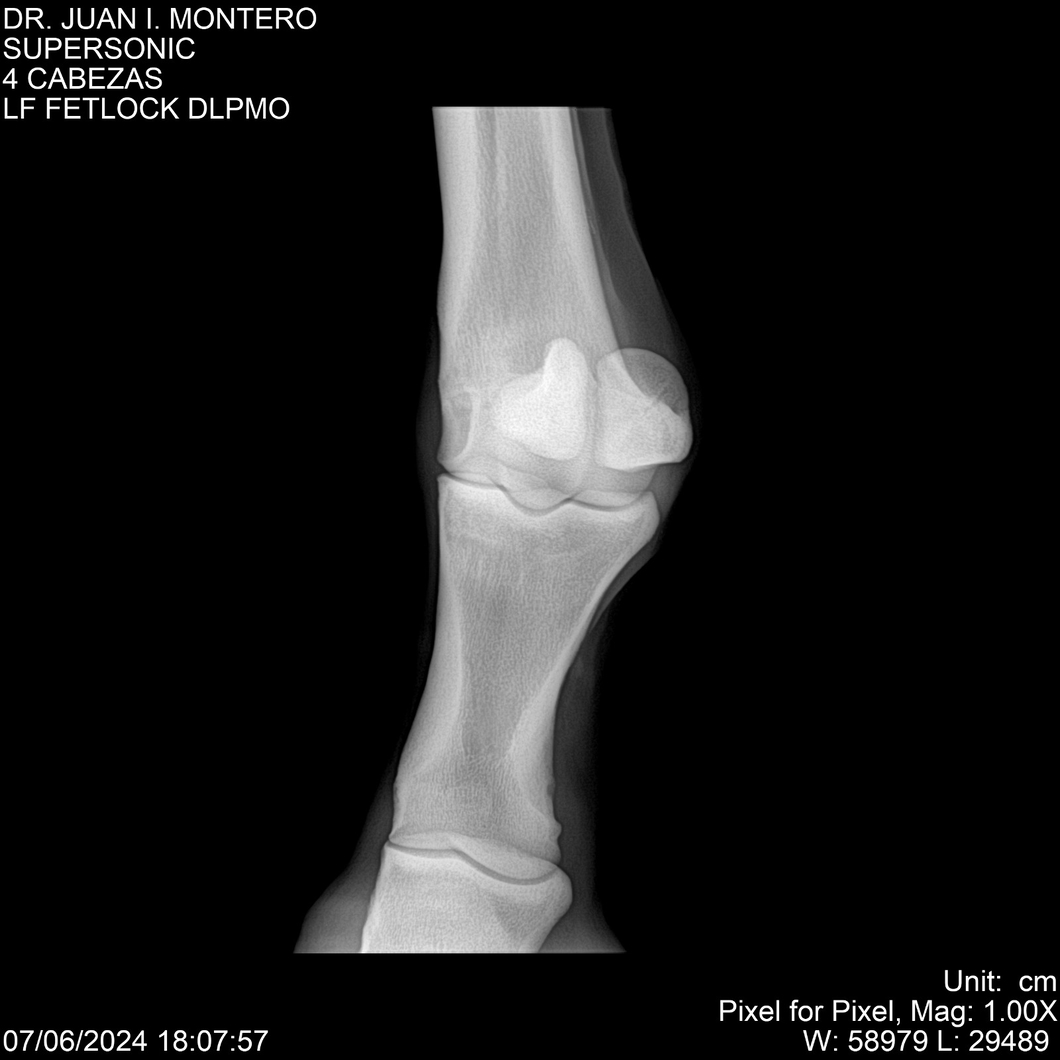

LOTE 5, SUPER SONIC Lote Anterior Volver al remate Lote Siguiente Ficha Contacto Montevideo - Ficha del Lote Identificador: #281089 Categoría: Yeguarizos Montevideo - 69 Visualizaciones ClicData Contacto Empresa: Abelenda N. R., Walter Hugo Nombre*: Teléfono* : E-mail* : Mensaje Enviar Registrese gratis Este contenido Exclusivo está disponible sólo para usuarios registrados Ingresar